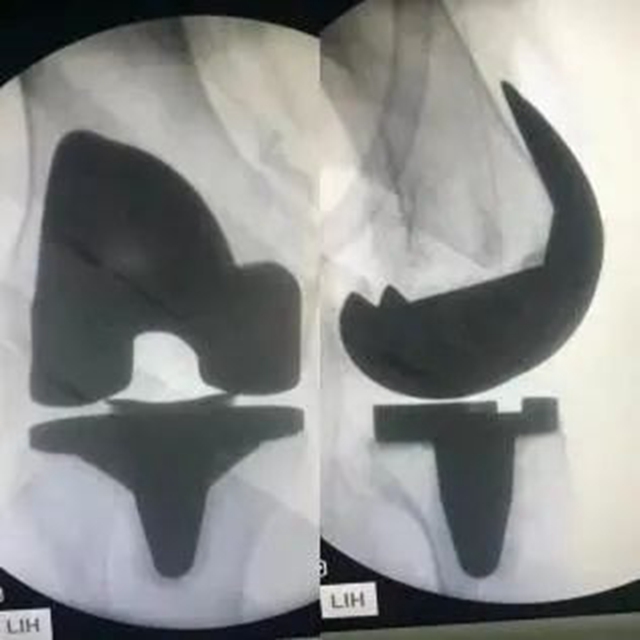

术后X片